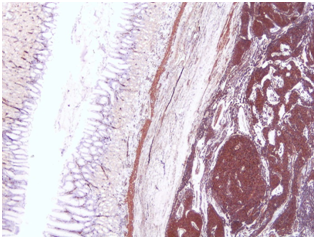

Under general anesthesia a laparoscopic exploration was performed. A 3cm tumor was found at the posterior wall of the stomach (Figure 2). There were no other pathological findings during the exploration of the abdomen cavity. A wedge resection of the tumor was performed using laparoscopic staplers. The patient had uneventful recovering period and was discharged 5days after surgery. On slides taken from lesion showed the round cells with small uniform nuclei, without nuclear pleomorphic and no mitotic figures. The distribution of round glomus cells around the open vascular lumen is a key to the pathology diagnosis. The lesion was positive for alpha-smooth muscle Actine (alpha SMA), Calponin and negative for CD-34, C-KIT and CK MNF116. The proliferating marker showed very low mitotic rate, less than one per 50 HPF. The histological examination and immunohistochemical stains confirmed diagnosis of gastric glomus tumor (Figure 3). The surgical resection margins were free of tumor.

Figure 3 The histological examination and immunohistochemical stains of gastric glomus tumor.